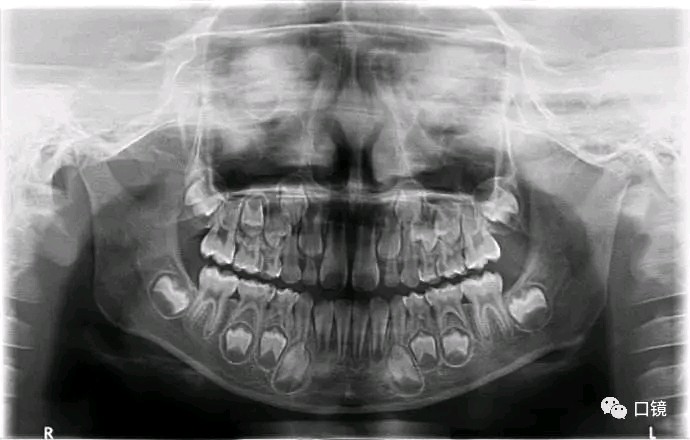

乳牙20颗,恒牙28-32颗。

2.牙齿可分为切牙、尖牙、双尖牙和磨牙4种。每个牙齿均由露在牙槽骨外的牙冠和长在牙槽骨内的牙根,以及牙冠、牙根之间的牙颈组成。